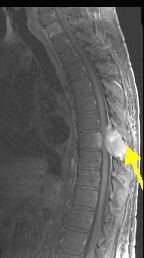

Metastatic Spinal Cord Compression

Metastatic epidural spinal cord compression (MESCC) occurs when cancer metastasises to the spine or epidural metastatic spinal cord compression: a prospective study using multivariate analysis of variables infl uencing survival and gait ... Doc Retrieval